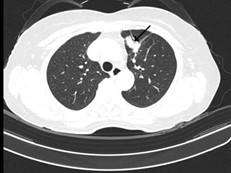

- Cắt lớp vi tính ngực (Bệnh viện Bạch Mai): phổi trái: phân thùy S3 có khối tỷ trọng tổ chức kích thước 18x26mm, bờ không đều ranh giới không rõ với màng phổi trung thất, lân cận có vài dải xẹp. Nốt bán đặc nhỏ thùy dưới đường kính khoảng 4mm. Vài hạch trung thất đường kính <10mm. Xương đòn trái có đậm độ không đều kèm dày vỏ xương đoạn 1/3 trong. Khoang màng phổi hai bên không thấy dịch – khí.

Hình 3: Cắt lớp vi tính lồng ngực sau 3 tháng điều trị bằng Osimertinib cho thấy khối u phổi trái tại phân thùy S3 giảm kích thước (mũi tên đen), hạch trung thất thoái triển, tràn dịch màng phổi giảm.

Nhận xét: Sau 3 tháng điều trị đích bằng Osimertinib (80mg/ngày), bệnh nhân ghi nhận đáp ứng điều trị rõ rệt. Lâm sàng cải thiện tốt. Trên cắt lớp vi tính lồng ngực, khối u phổi trái giảm kích thước, hạch trung thất thoái triển, tràn dịch màng phổi giảm đáng kể. Theo tiêu chuẩn RECIST 1.1, bệnh nhân được đánh giá đáp ứng 1 phần. Sau 6 tháng điều trị đích, bệnh nhân cải thiện rõ về mặt lâm sàng, toàn trạng ổn, xét nghiệm chất chỉ điểm khối u giảm rõ rệt, cắt lớp vi tính bụng, não không ghi nhận tổn thương thứ phát. Kết quả cho thấy hiệu quả kiểm soát bệnh kéo dài của Osimertinib.